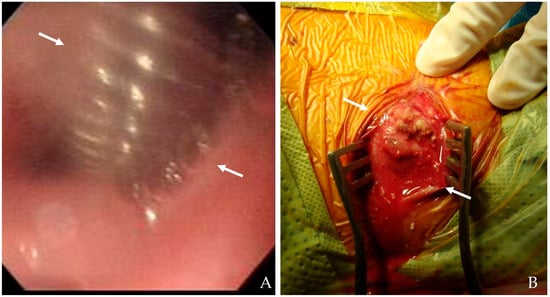

Direct visualization through flexible esophagoscopy allows for identifying the exact location and size of mucosal tears, inflammatory changes, and esophageal defects [20,22]. Because this procedure avoids using contrast agents, it is particularly safe in patients with suspected perforations. Endoscopic evaluation facilitates therapeutic interventions in certain cases, such as stent placement (Figure 5). Innovations in endoscopic imaging, including high-definition endoscopy and narrow-band imaging, have enhanced diagnostic accuracy and enabled targeted therapeutic interventions [24].

Figure 5. The patient underwent C5-6-7 anterior cervical discectomy and fusion (A). At postoperative 2 months, postoperative infection occurred, and flexible esophagoscopy showed esophageal rupture (white arrows) (A). Therefore, the patient underwent evacuation of retropharyngeal abscess (white arrows), irrigation/debridement, and primary repair of esophageal rupture (B).